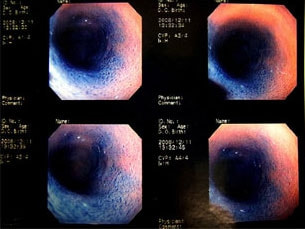

症例:炎症性ポリープ M.ダックス 10歳 オス

主訴:8ヶ月前から便が細くなり、血が混じることがある。その他、元気・食欲等、一般状態は良好。

経過:超音波検査にて直腸壁の肥厚(5㎜)が認められた。また、直腸検査で直腸全周に結節状病変を触知し、出血も確認された。消炎剤、抗生剤、整腸剤による治療への反応が長期的に悪いため、生検も含めた内視鏡検査を実施した。

内視鏡検査:肛門付近の直腸全周に、炎症および出血を伴う結節状病変を多数認めた。

病理検査:直腸の病変は、良性の非腫瘍性病変の一つである“炎症性ポリープ”と診断された。

診断後経過:炎症性ポリープは多発する傾向や腫瘍に転化する可能性があるため、消炎剤、抗生剤、整腸剤による内科療法を継続しながら、現在プルスルー法による外科的摘出術を検討中。

◎炎症性ポリープとは

近年、ミニチュアダックスで好発が知られている良性の腫瘍性の病変です。しばしば多発し、また腫瘍に転化する事があります。